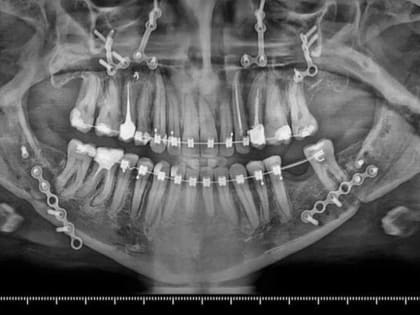

Волгоградские челюстно-лицевые хирурги исправили пациентке неправильный прикус

Фото: Волгоградский облздрав К специалистам женщина обратилась с многочисленными жалобами, включая неудовлетворенность эстетикой лица.